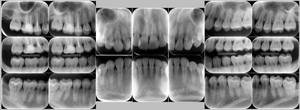

レントゲン写真

症例

治療内容 1.歯周ポケット検査、資料取り(レントゲン写真14枚・口腔内写真)、歯磨き指導

4.再評価(歯周ポケット検査・レントゲン写真14枚・口腔内写真)